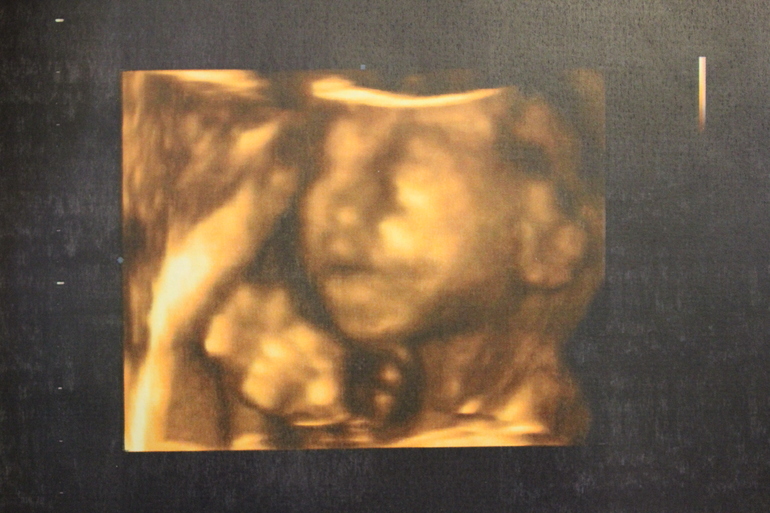

УРРРРАААААААААА!!!!!!!!!!! УЗИ в 21 неделю)))))))

Согласна с комментом ниже..только увидела фото первое сразу мысль мальчишка))) и точно..)))

25.01.2014

да..видно что мальчик..)))) настоящий мужичок)))

А я почему то только на личико глянула и думаю-мальчик. Потом почитала, и вправду. Поздравляю!